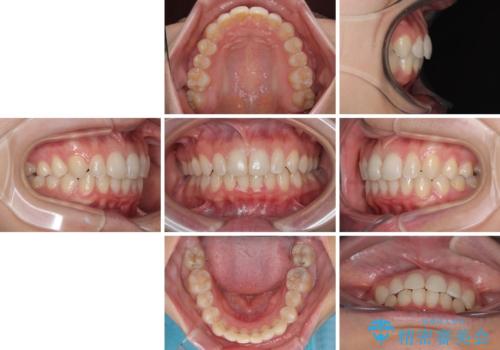

- 前歯のデコボコと歯肉に埋もれている奥歯を気にして来院された患者様です。

インビザラインでの治療を希望されていましたが、左右の下顎大臼歯が歯肉に埋もれており、特に右側は歯軸が顕著に傾斜していたため、インビザライン単独での治療は困難と判断し、ワイヤー装置を併用することとしました。

ワイヤー装置での下顎臼歯改善には時間がかかることが予想されたため、下顎のワイヤー矯正と並行して上顎をインビザラインで整え、その後インビザラインにより上下歯列を整える矯正治療を行うこととしました。

ワイヤー装置を併用したことで、レントゲン写真からも分かるとおり歯軸をしっかりと改善させることができました。